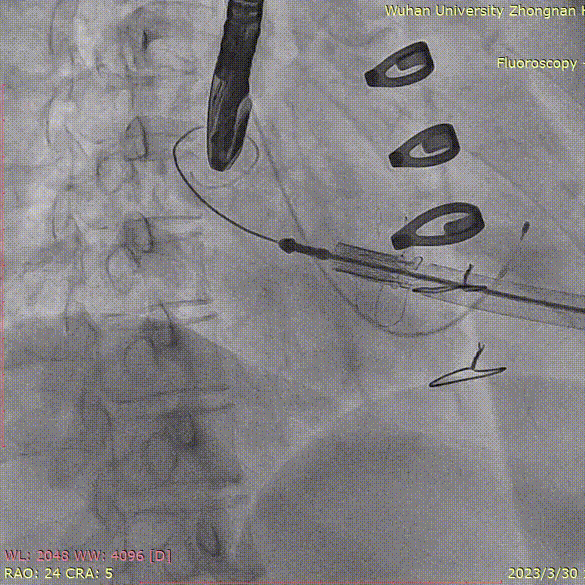

穿刺心尖、导丝跨瓣:

释放定位件,三个定位件均入瓣角,形态良好:

准备释放瓣膜:

释放瓣膜,先打开瓣膜鼻锥,形态位置满意后再让瓣膜完全释放:

原有生物瓣架提供支撑力,瓣膜得以持续膨胀,并获得良好形态: